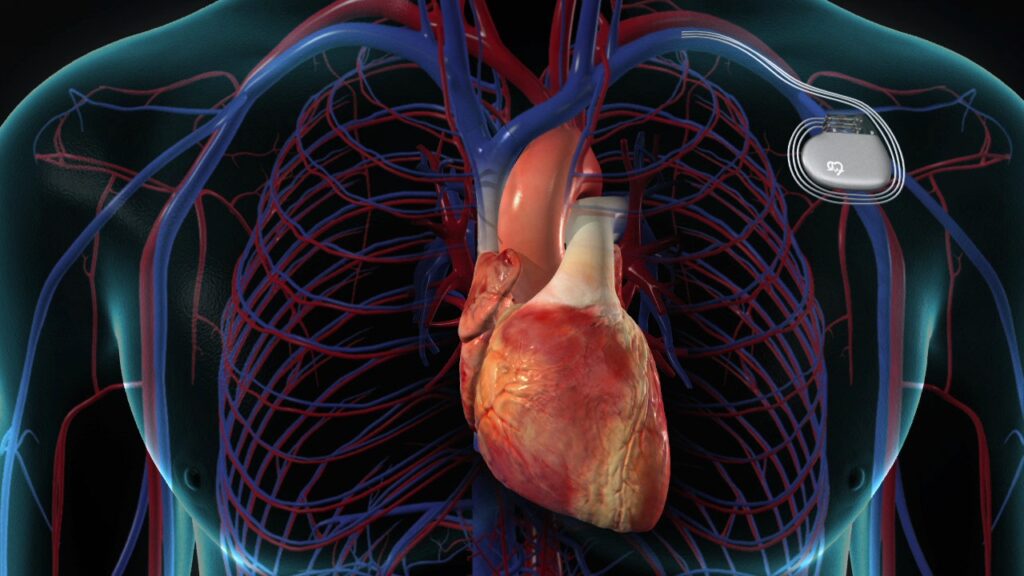

A pacemaker is a small, battery-powered device implanted under the skin, usually near the chest. It sends electrical signals to stimulate the heart whenever the heartbeat becomes too slow or irregular.

Permanent Pacemaker:

Implanted for long-term rhythm correction in conditions like complete heart block, chronic bradycardia, or certain arrhythmias.

Modern pacemakers are highly advanced, compact, and allow patients to lead an active, normal life.